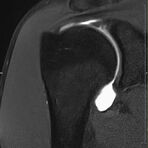

Gelenke

Hand

• Beurteilung von Knochen, Bändern und anderen Weichteilstrukturen der Gelenke nach Unfall.

• Impingement-Symptomatik

Arthrographie

• MR-Arthrographie – nach örtlicher Betäubung und gründlicher Desinfektion der Haut wird unter Lagekontrolle mit Röntgen-Durchleuchtung eine kleine Nadel in den Gelenkraum positoniert und darüber ein MR-taugliches Kontrastmittel in den Gelenkraum gespritzt. Danach wird die Nadel entfernt. Anschließend erfolgt die MRT des Gelenkes. Diese Methode stellt kleine anatomische Strukturen des Gelenkraumes verbessert dar, z.B. zur Therapieplanung vor Arthroskopie bei Sportverletzungen der Schulter oder Gelenkinstabilität.